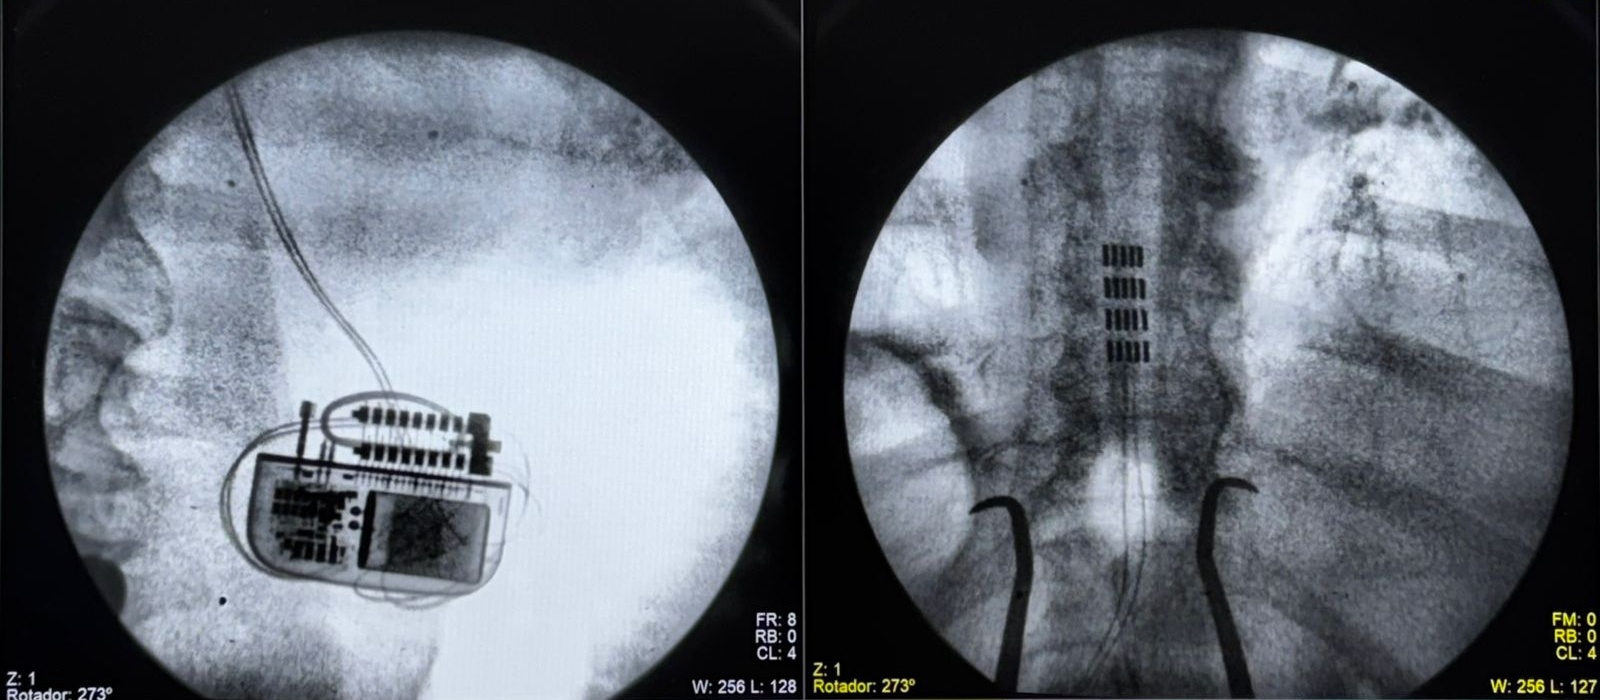

No. Es un procedimiento mínimamente invasivo. El dispositivo es el más pequeño del mercado (similar al tamaño de una moneda grande) y se coloca bajo la piel en la zona glútea o lumbar mediante una incisión pequeña. La recuperación es rápida y la mayoría de los pacientes regresan a su casa el mismo día o al día siguiente.